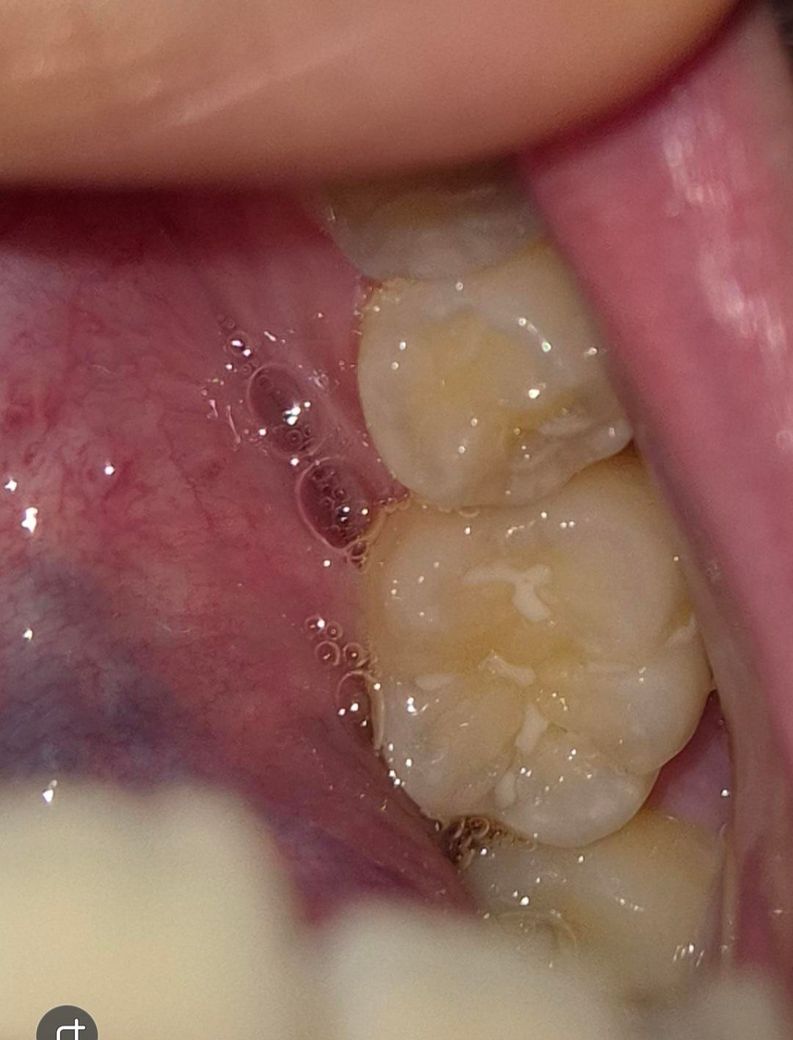

아이 어금니 실란트 떨어진 부위? 충치인건지요

어금니 동그라미친 부분인데요 , 실란트가 부분부분 삭제되긴했어요 근데 유독 저부분만 뒤쪽이긴하지만 각도때문인건지 신경쓰여서요 치과에서는 충치는아니고 실란트가 떨어져서 그렇고 빛에따라서 음영? 암튼 눈으로보면 뭐가껴있거나 그런식으로 색이 보여질수는있다고, 치과빛으로비춰 거울로보고 검진해도 충치는아니라고하셨는데 .. 왤케신경이 쓰이는건지.. 제가 어떤각도에서보면 유독저부분이 진짜뭐가껴있거나 충치같은색으로 보이기도하고 또어떤각도에선 괜차나보이기도하고 그러긴해요 ㅜㅜ 다른전문가분들의 의견이궁금합니다